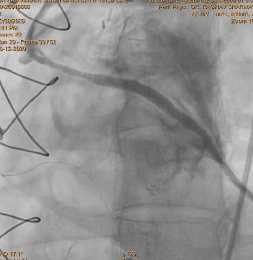

After deployment observed Perforation of SVG-OM Distal LCX post Stenting.

Used two covered stent to cover perforation OM and LCX .

After using covered stent perforation was sealed and TIMI 3 flow achieved

Patient was stable and all parameter was normal and discharge after two days from hospital